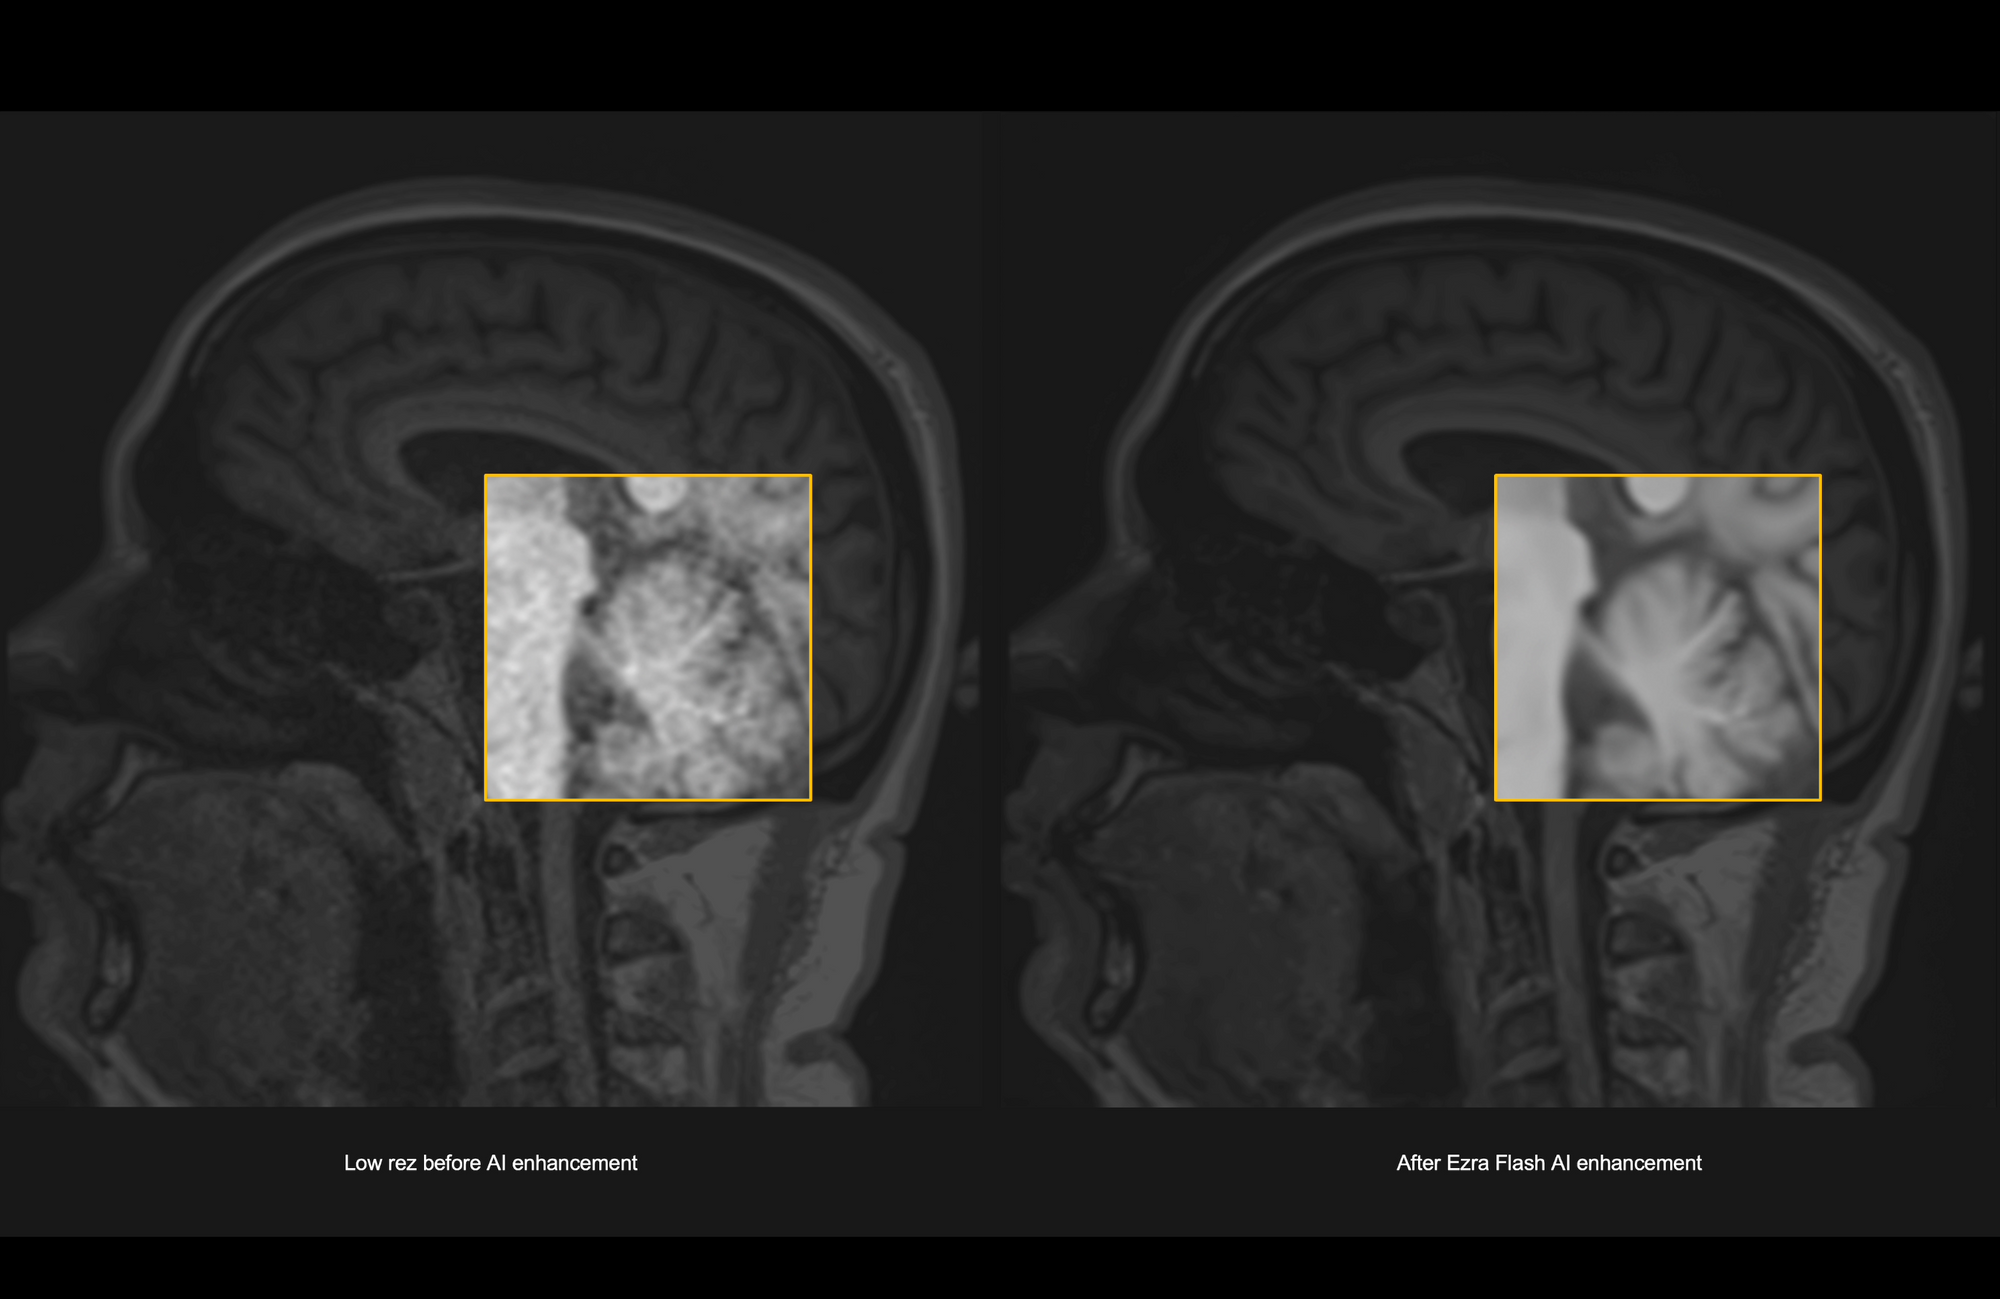

Today, I’m incredibly excited to announce that we have received 510(k) FDA clearance for the Ezra Flash AI, enabling us to roll out the world’s first 30-minute full body MRI. The new AI reduces noise and improves the quality of MRI images, enabling us to create a scanning protocol with twice the speed and same image quality.

Here's an example:

That’s Step 2, done. You can now book your 30-minute Ezra Flash Full Body here for $1,350.